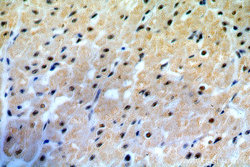

Immunohistochemistry

19420-1-AP IHC